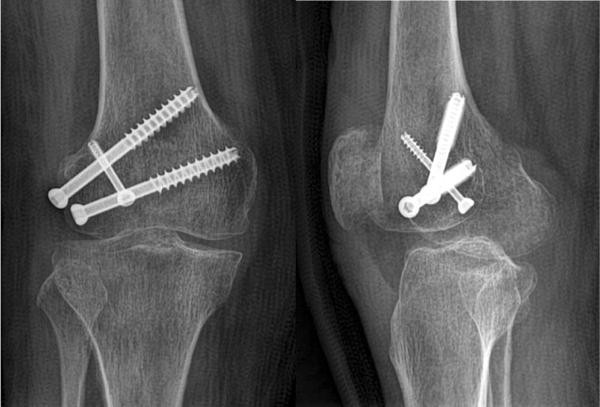

Jcdr Bilateral Hoffa Coronal Fracture Distal Femur - Hoffa fracture is a type of distal condylar femoral fracture and is characterized by an associated fracture component in the coronal plane.

A 31 Year Old Male With A Hoffa Fracture Of The Lateral Femoral Condyle Download Scientific Diagram - posterior tangential fracture of one(usually lateral) or both femoralcondyles.

Arthroscopic Management Of A Posterior Femoral Condyle Hoffa Fracture Surgical Technique Arthroscopy Techniques - A hoffa fracture was found over the lateral femoral condyle, with the condylar fragment displaced fig 2.

Figure 3 A New Fixation Method For Hoffa Fracture Springerlink - The hoffa fracture is a rare fracture pattern consisting of a unicondylar posterior fracture.

Distal Femur Fractures Trauma Orthobullets - Lateral femoral condyle fractures in 80%.

A Rare Case Of Unicondylar Medial Hoffa Fracture Associated With Ipsilateral Vertical Patella Fracture Journal Of Clinical Orthopaedics Trauma - Unicondylar fractures of the femur that occur in the coronal plane (hoffa fractures) are uncommon.